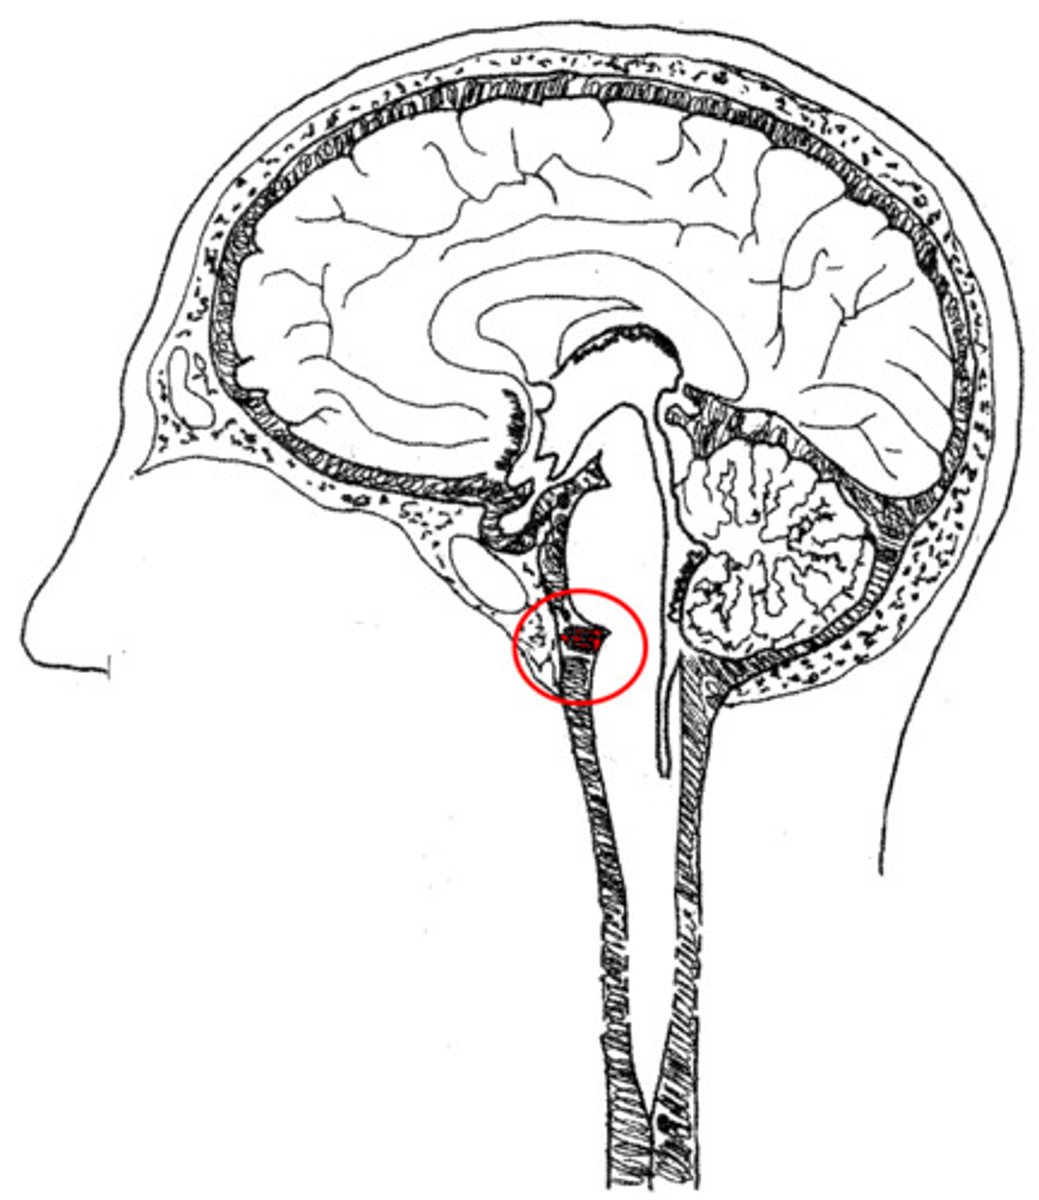

cervicomedullary junction

transition between the medulla oblongata and upper cervical spinal cord (C1-C2) that is located at the level of the foramen magnum

*houses ascending/descending tracts (decussation) and nuclei that influence breathing, CV control, and CN 9-12

*orange line on picture

tonsillar herniation

herniation of the brain where cerebellar tonsils descend through the foramen magnum

foramen magnum

large opening at the based of the skull that transmits the spinal cord, vertebral arteries, and spinal accessory nerve (CN XI)